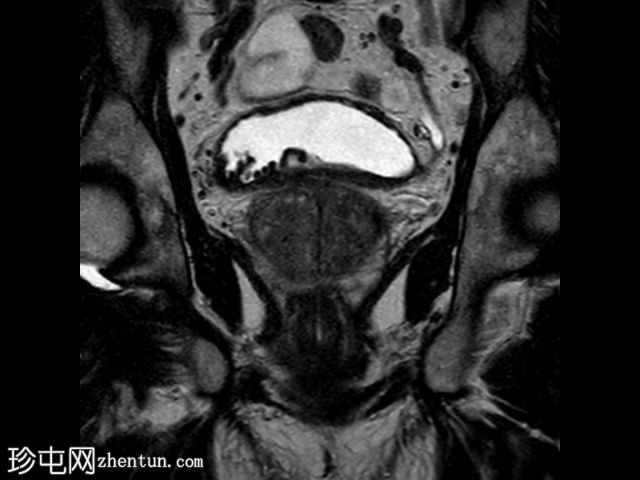

冠状位

T2加权像

在T1和T2加权像上,于膀胱底部及右下外侧面偶然发现一处呈蛇形缠绕状的低信号区。动态序列中可见快速对比增强,提示所有影像学表现均源于血管,信号缺失与动静脉畸形有关,该畸形至少由膀胱下动脉供血,并由同侧局部扩张的静脉回流。